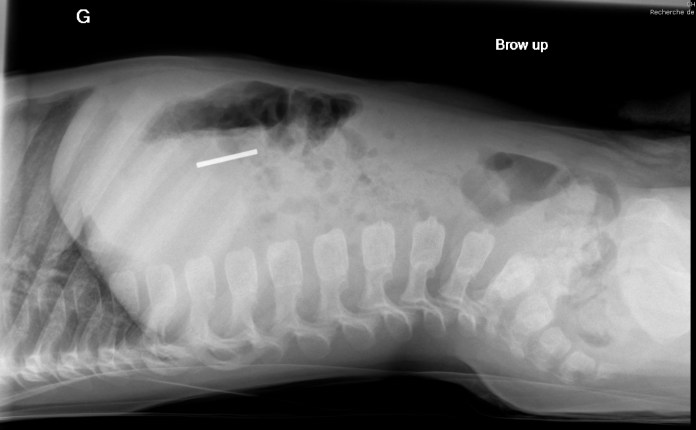

Conseils du doc vol. 7

👉🏿 Enfants:  il ne faut pas confondre les clous, les vis, les clés USB avec des sucettes.

👉🏿 Parents: rangez bien vos boite à outils…

À ce rythme là je vais finir par ouvrir une quincaillerie 😂

🔨🛠⛏🗝